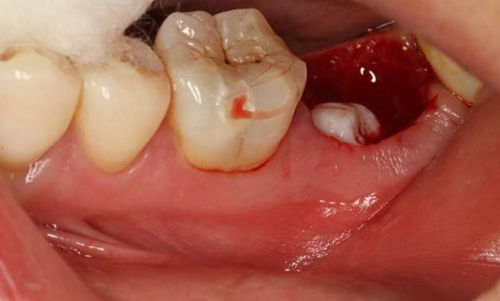

圖3.   取出棉球口內(nèi)發(fā)現(xiàn)37合面有開髓孔,探針出血,頰側牙齦紅腫。

3.jpg